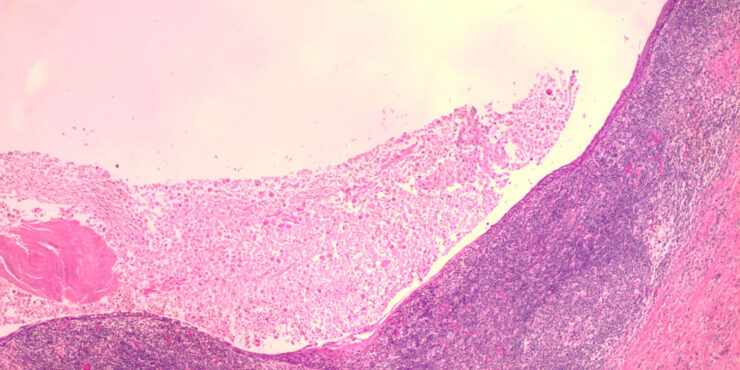

Branchial cleft cyst =كيسة الشق الغلصمي Branchial Cyst (Branchial Cleft Cyst) Sequestration of first or second branchial cleft membranes results in these cysts, sinuses, or tags. EPIDEMIOLOGY Branchial cleft cysts are largely sporadic, but autosomal dominant cases have been reported. There is no gender predominance. Ten percent of lesions are bilateral. ETIOLOGY AND […]